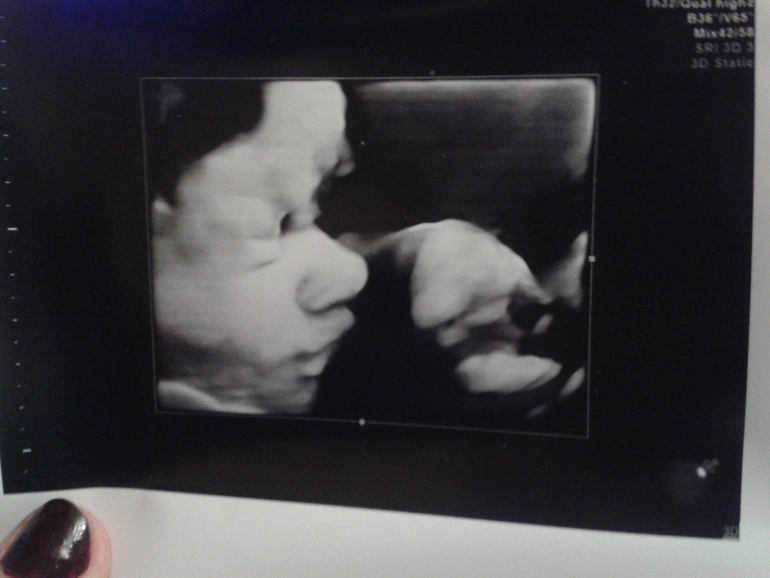

Иииииии....она показала личико! Опухшее пока еще, но уже видно,что там копия муж)))Прилагаю фото для сравнения...))

Да вообще папин профиль))Разве что брови вроде мои намечаются)))

Посмотрим)))Они и меняются в течение детства только так внешне, муж вон вообще родился копия бабушка по отцу, а сейчас он в свою мать.Я родилась копия папа,а сейчас больше мама))Но тут профиль явно не мой.)По крайней мере нос и губки точно не мои, бровки вроде мои будут ))